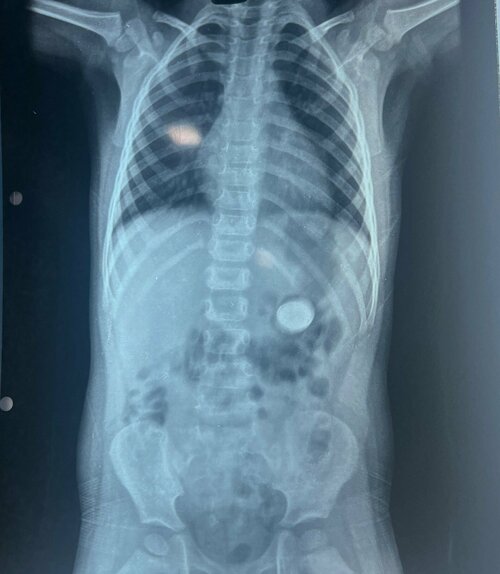

Pulse Hospital Successfully Completes 7th Pediatric Foreign Body Removal Case

In a remarkable feat, the team at Pulse Multi-Speciality Hospital successfully removed a lithium battery from the stomach of a 3-year-old child. Lithi...